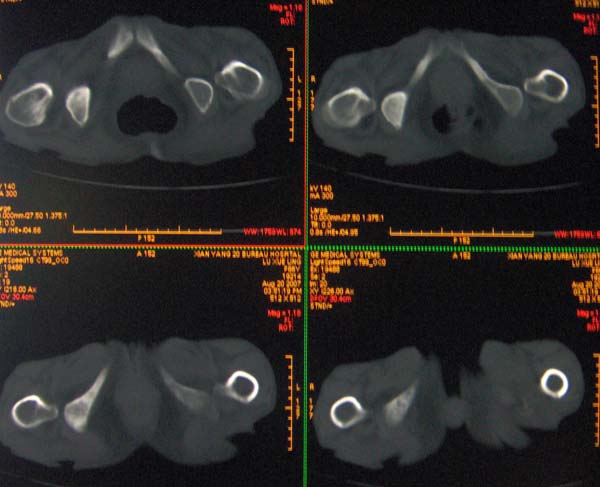

以下是引用ybing在2007-8-22 20:31:00的发言:[br]左侧髂骨溶骨样破坏;软组织肿块形成;其内未见肿瘤骨考虑纤维肉瘤或滑膜肉瘤不除外转移瘤

以下是引用qiushi在2007-8-22 21:39:00的发言:[br]双侧髂骨、骶骨侧快呈溶骨样骨质破坏,边缘模糊,左侧髂骨见骨折线,左侧髂部见软组织块影。考虑骨纤维肉瘤(中央型)伴病理性骨折,不排除骨髓瘤。建议本--周氏蛋白检查。[br] 鉴别点:[br] 骨纤维肉瘤,中央型者示边缘模糊的囊状溶骨破坏,一般无骨膜反映,可膨胀变形,突破骨皮质可形成软组织肿块,或并发病理性骨折。[br] 骨髓瘤,常表现为广泛的骨质疏松,皮质变薄或破坏,呈粟栗状、穿凿状、鼠咬状骨质破坏,边缘清晰,周围无硬化。[br] 骨转移瘤(溶骨型),表现为虫噬样、泡沫状圆形或卵圆形破坏区,很少出现软组织块影。[br][br][本贴已被 qiushi 于 2007-8-23 6:20:19 修改过]